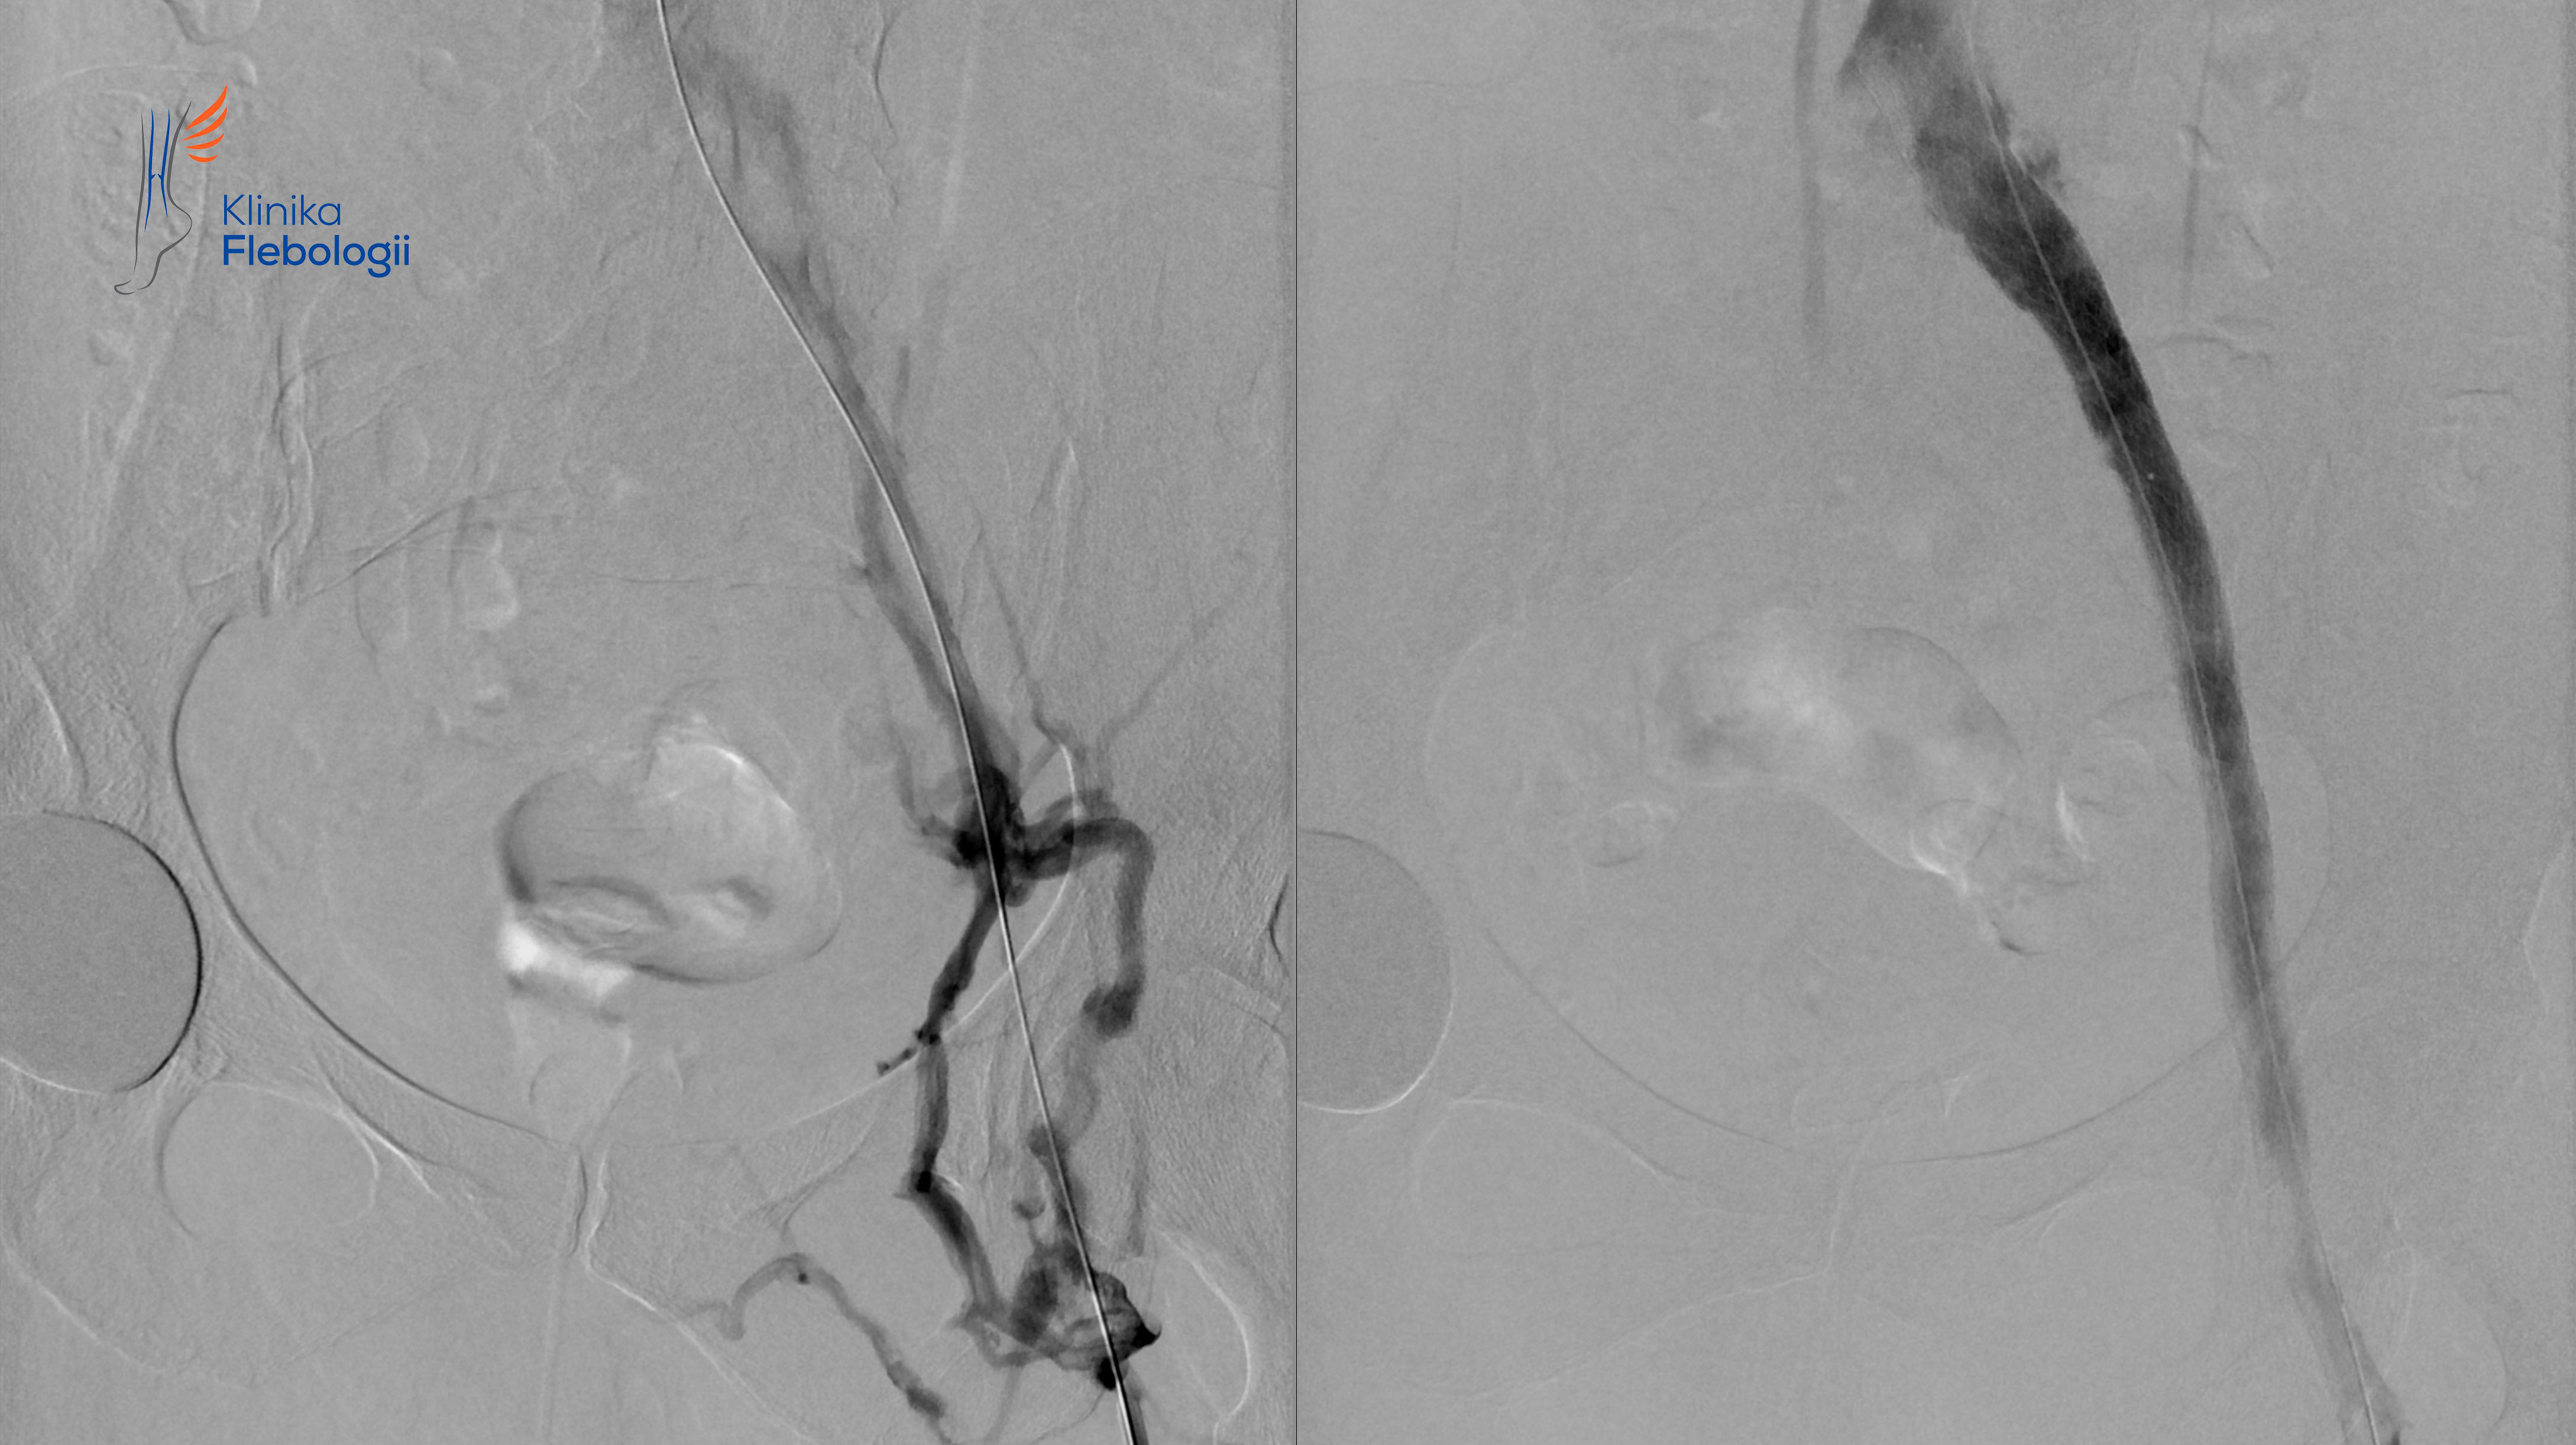

Zespół May-Thurnera. Stentowanie.

Stan po stentowaniu lewego spływu biodrowego w przebiegu zespołu May-Thurnera.

Rzadka postać żylnego zespołu uciskowego na poziomie spływu lewej żyły biodrowej wspólnej.